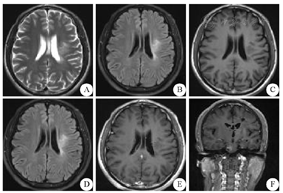

2018年5月15日患者自觉右侧肢体无力较前加重,可自行行走,无持物不稳,伴言语不清,无发热、咳嗽及咳痰,无头痛、恶心及呕吐,无肢体抽搐及意识障碍。为求诊治,于2018年5月23日以"炎性脱髓鞘性假瘤"收入临沂市人民医院神经内科。入院体检:体温36.6 ℃,心率80次/min,呼吸20次/min,血压92/64 mmHg(1 mmHg=0.133 kPa)。发育正常,营养良好,心肺腹部体检无异常,双下肢无水肿。神经系统体格检查:神志清,精神可,口齿欠清晰。听、理解力正常,高级认知能力正常。双侧瞳孔等大等圆,直径3 mm,直接、间接对光反应灵敏,双眼各向运动及边,无震颤。双侧额纹对称,双眼睑闭合有力,右侧鼻唇沟浅,口角向左侧歪斜,伸舌右偏,右侧鼓腮漏气。余颅神经查体未见异常。右上肢肌力5级,右下肢肌力4级,左侧肢体肌力5级,四肢肌张力正常,右侧巴宾斯基征(+),左侧巴宾斯基征(-)。双侧肢体腱反射对称(++),双侧髌阵挛、踝阵挛(-),双侧指鼻试验、跟-膝-胫试验(-),Romberg征(-),深浅感觉无异常。辅助检查:小生化、血常规、凝血四项、尿液分析、感染六项均未见异常。2018年5月22日患者行颅脑MRI检查(平扫+强化)显示:左侧额叶、基底节区、丘脑、侧脑室旁见大片混杂信号,T1WI呈等低信号,T2WI呈等高信号,T2 FLAIR呈高/低信号,DWI显示部分高信号、局部低信号,注射钆喷酸葡胺对比剂后,未见明显强化(图3)。结合病史、体征及辅助检查结果,患者诊断"炎性脱髓鞘性假瘤"明确。经家属同意后,给予大剂量甲泼尼龙降阶梯法冲击治疗,初始给予甲泼尼龙500 mg静脉滴注、1次/d,每3天依次减半,最低减至甲泼尼龙40 mg静脉滴注,3 d后予以泼尼松片35 mg口服、1次/d,并予以出院。

A~C:平扫;D:DWI;E、F:增强扫描;DWI:弥散加权成像